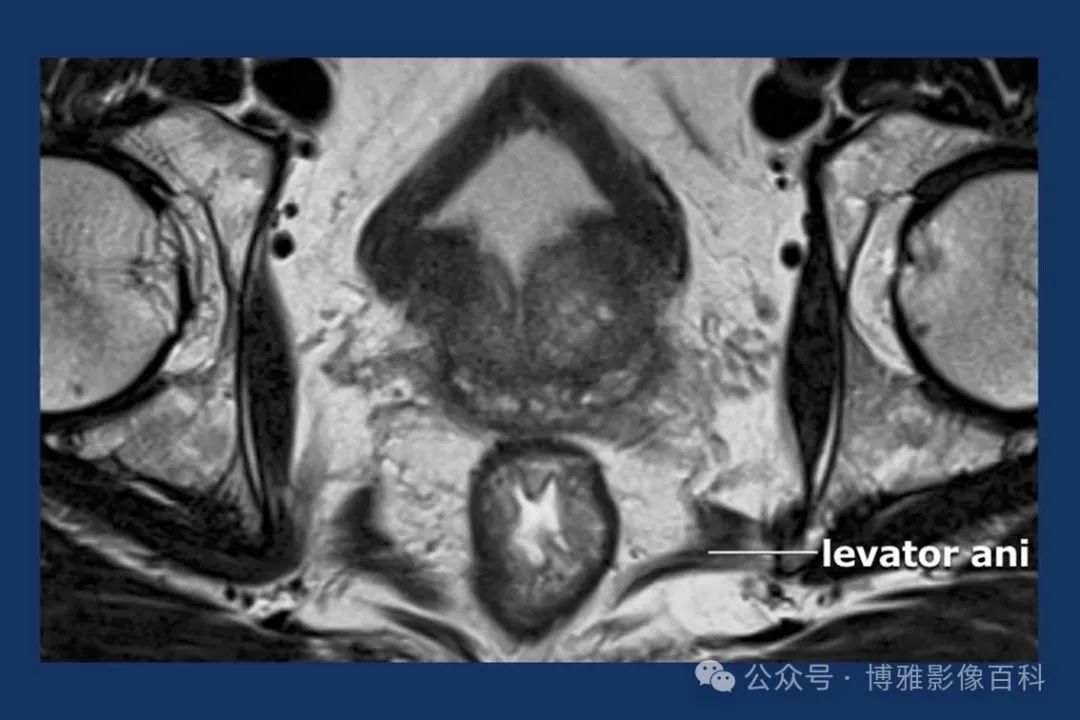

MR 解剖学

前列腺良性增生患者的轴向T2 图像,其他方面正常。外周带是一薄层均匀的高信号,边界清晰连续性的低信号包膜。移行带通常表现为不均匀中等信号,病灶被边界清楚的BPH良性前列腺增生结节所取代。精囊具有均匀T2高信号。未见淋巴结肿大。